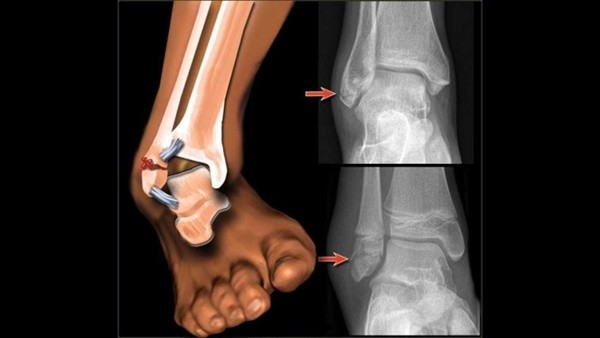

한편 높은 곳에서 뛰어내리거나 과격한 운동을 하다가 염좌가 발생한 경우에는 골절 유무도 확인해봐야 한다. 이를 위한 진단법으로는 오타와 룰(Ottawa rule)이 있다. 오타와 룰은 민감도 100%의 진단법으로 발목의 골절이 의심될 때 우선적으로 적용한다.

안과 바깥 복숭아뼈에서부터 위로 6cm까지, 새끼발가락에서 발목까지 이어지는 뼈(중족골 기저부), 발등에서 90도가 되는 부분의 앞쪽 튀어나온 뼈(주상골)을 눌렀을 때 통증이 심하거나 그로 인해 4보도 걷기 힘든 경우는 골절을 의심한다.

오타와룰에서 양성반응이 보이면 X-ray검사를 받아야 한다. 만약 골절이 확진되면 염좌에 해당하는 보존적 치료 외에도 골절을 치료하는 한약을 복용해야 한다. 환자의 상태와 체질에 따라 다르겠지만 보통 녹용, 보골지, 속단 등이 포함된 약이 처방된다.